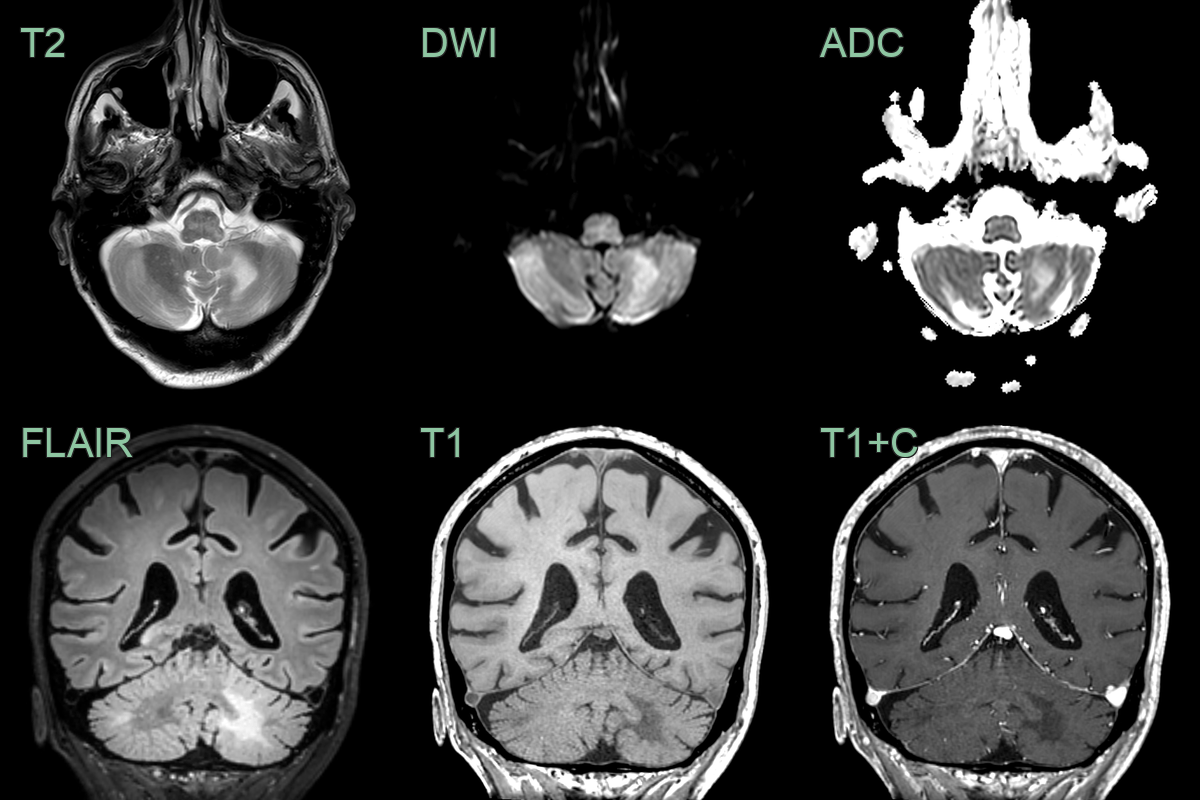

- 70-year-old patient undergoing treatment for lymphoma. Presented with seizures, confusion, and aphasia.

- MRI showed peripheral FLAIR-hyperintense and T1-hypointense lesions extending up to the cortex with no mass effect or enhancement.

- After one month and treatment with pembrolizumab, the lesions had enlarged with a more obvious leading edge of diffusion weighted hyperintensity. There was no contrast enhancement to suggest PML-IRIS.